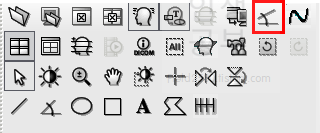

저 같은 경우는 Cobb 각도를 많이 사용하기 때문에 우선 Cobb각도 설정하는 방법에 대해서 알려드리겠습니다. 카테고리칸에 주석을 눌러주면 다양한 각도나 선, 모양을 그릴 수 있는 버튼이 나옵니다. 그중 상단 3번째 있는 버튼이 Cobb각도 그리기 입니다.

Cobb각도 그리기 버튼을 클릭해주고 아래로 쭉 내려주면 현재 사용하고 있는 도구상자에 Cobb각도 그리기 버튼이 추가되는 것을 확인하실 수 있습니다.

위와 같은 수고를 덜기 위해서 Display Workstation 프로그램에서는 간편하게 Cobb 각을 측정 할 수 있는 도구가 있습니다. 위에서 설명해 드린바와 같이 Cobb 각이 따로 있는데 각도 측정하는 버튼은 두 선이 연결된 반면 Cobb 각 버튼은 두 선이 떨어진 모양으로 되어있습니다. 빨간 네모 안에 있는 것이 Cobb 각 버튼입니다.